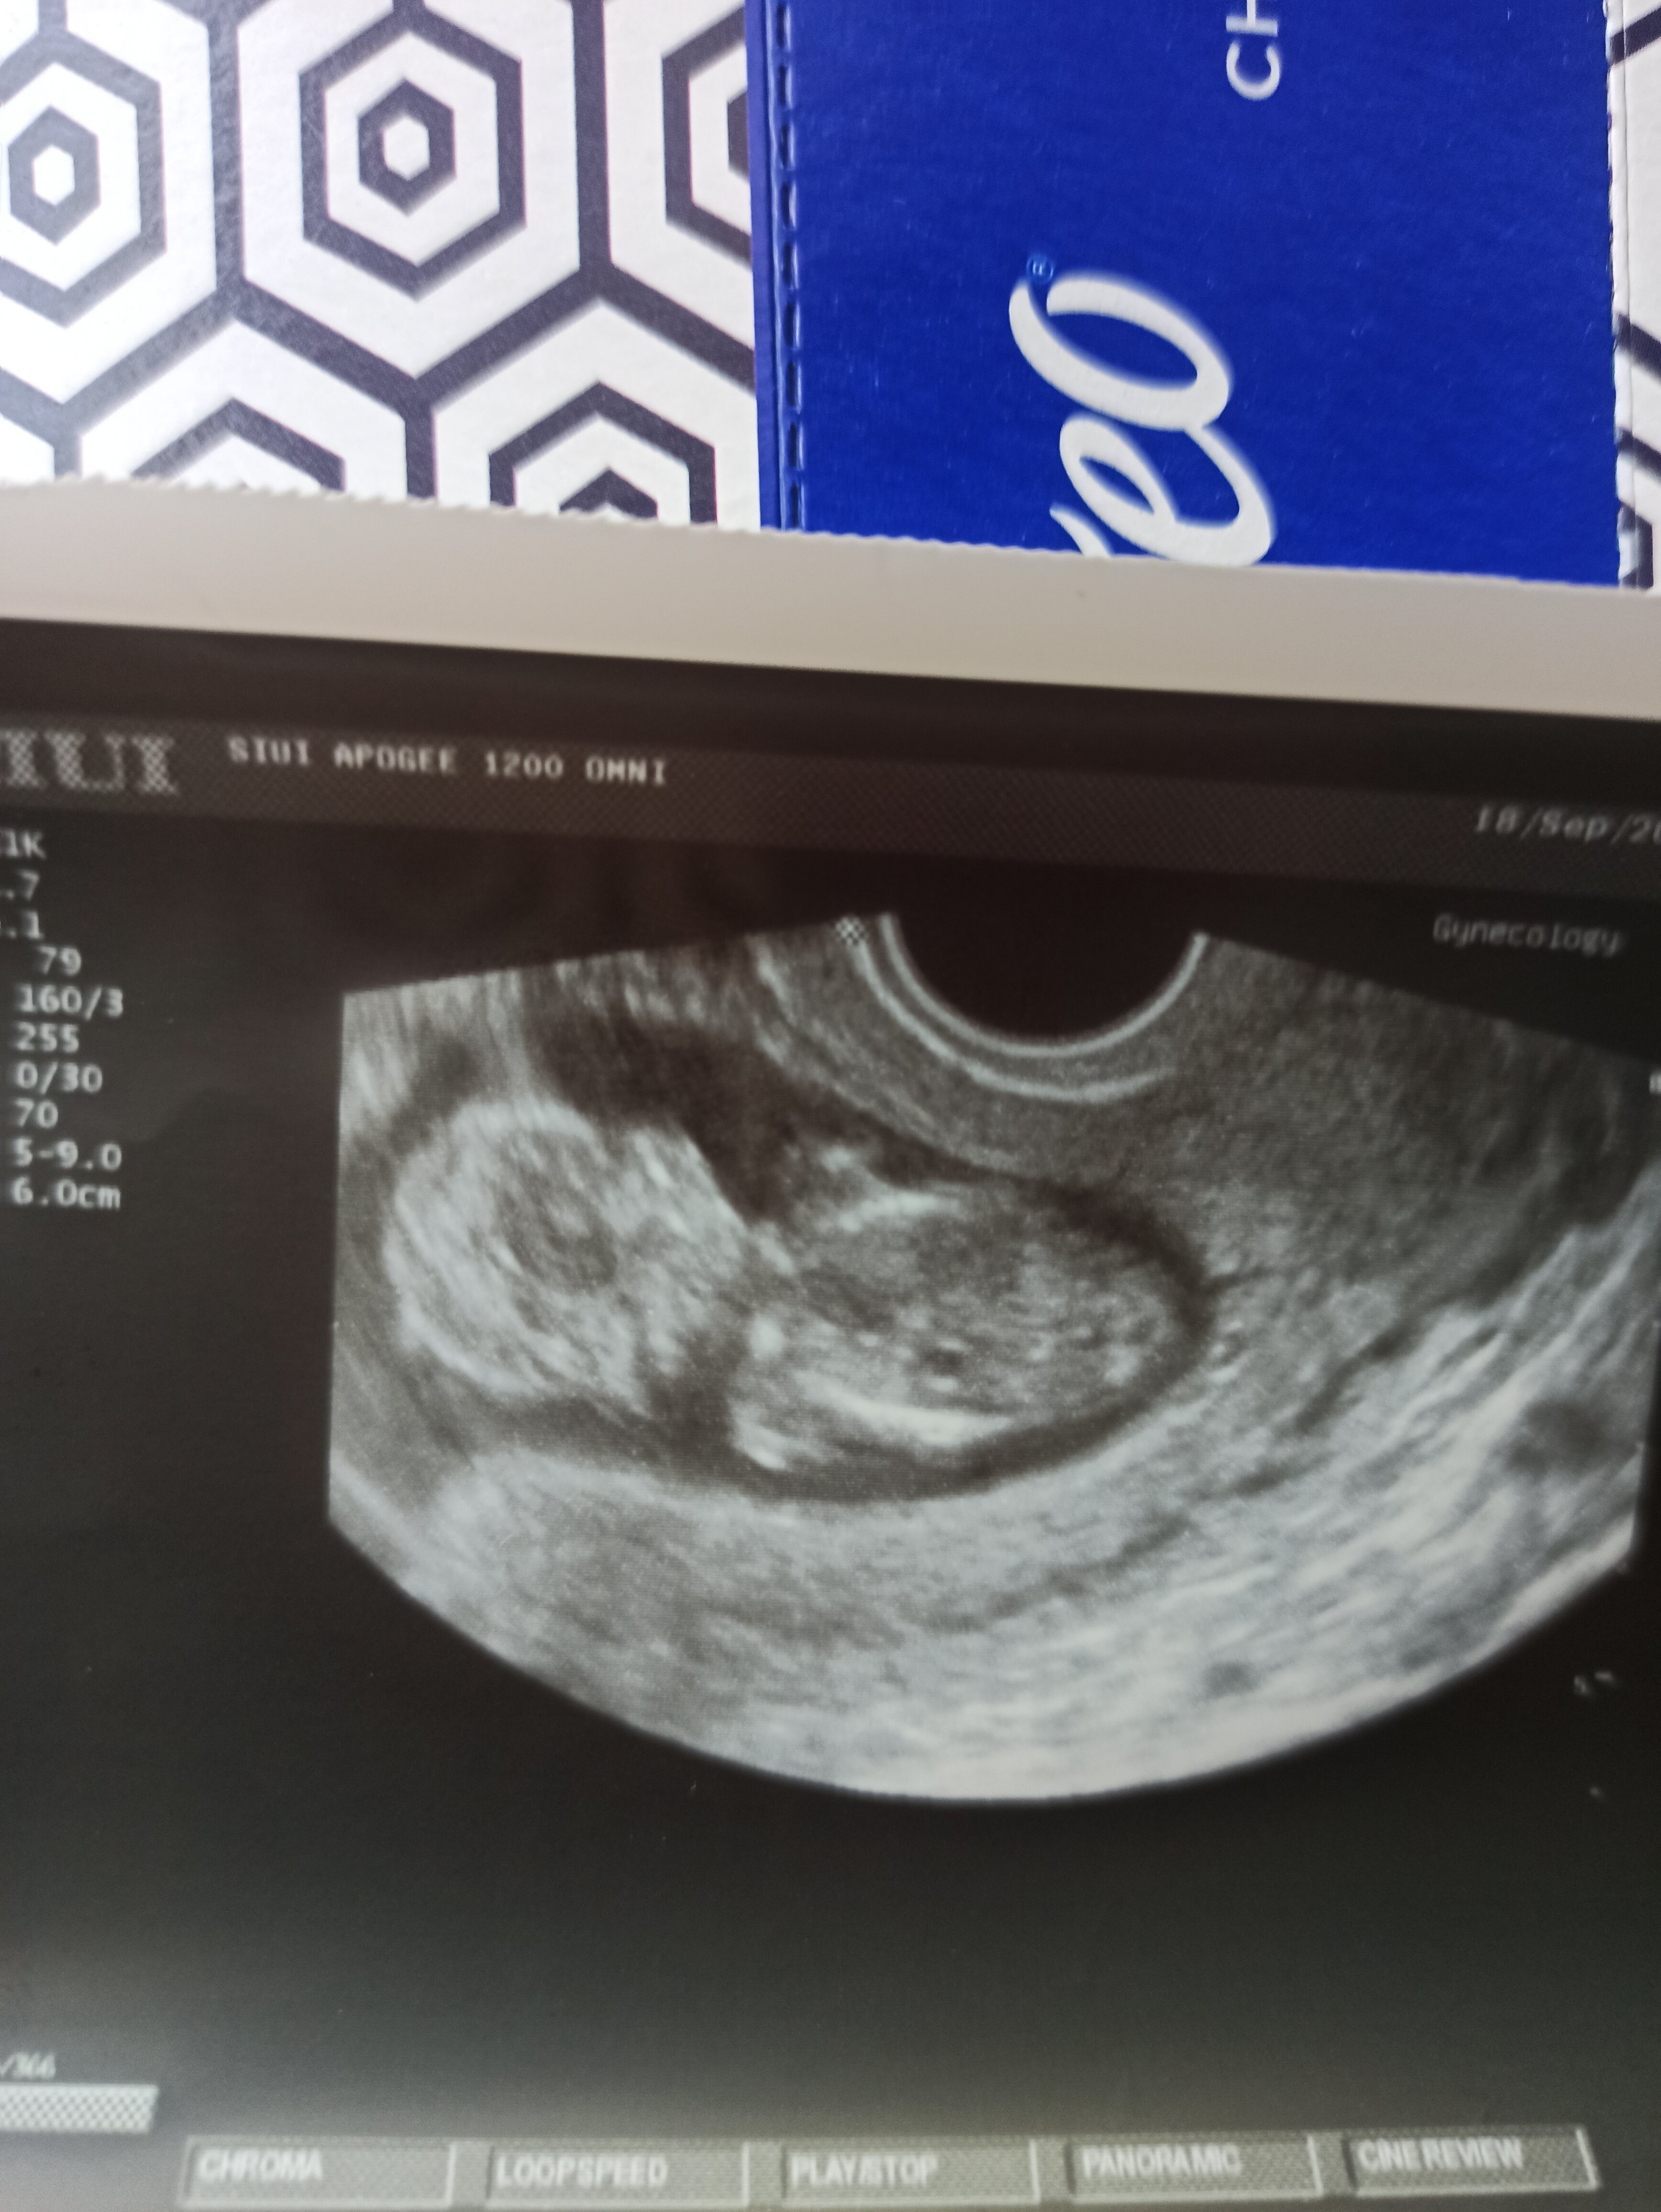

Hej dziewczyny, ja dzisiaj po wizycie kontrolnej. chyba wszystko ok bo Pani doktor nie Mogła zmierzyć dzidka tak się ustawialo, próbowała Parę razy i odpuściła. Jedynie to słyszałam piękne mocne serduszko

• IMG_20230918_093227.jpg

IMG_20230918_093227.jpg

1,5 MB · Wyświetleń: 90

to ruchliwy człowieczek 🥰 ale już duża dzidzia na usg 😍